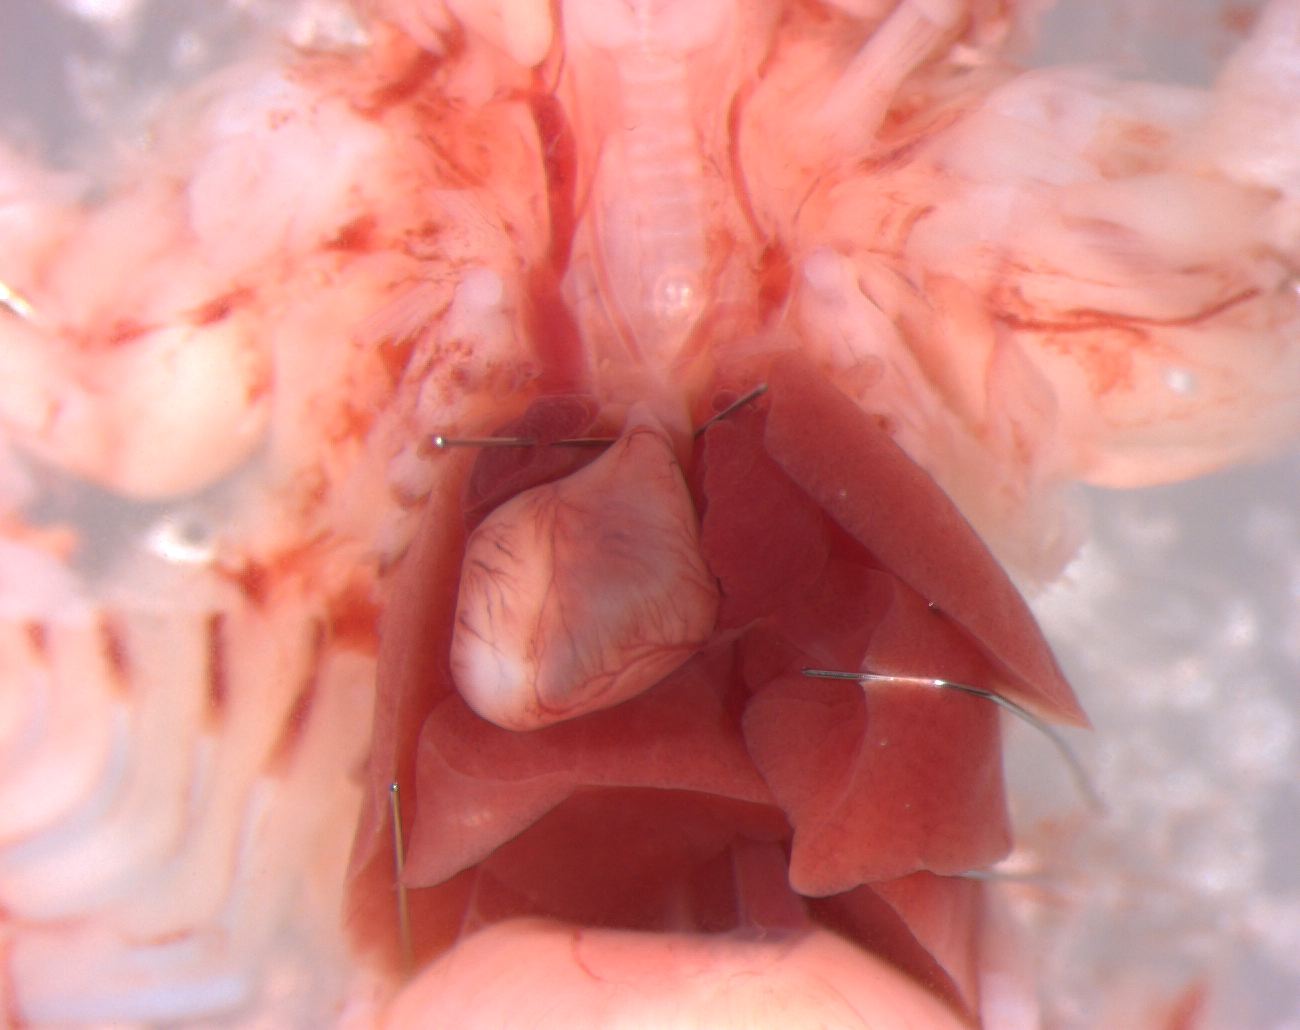

Caption Mutant 811-018-LA exhibits situs inversus totalis with dextrocardia and inverted lung lobation